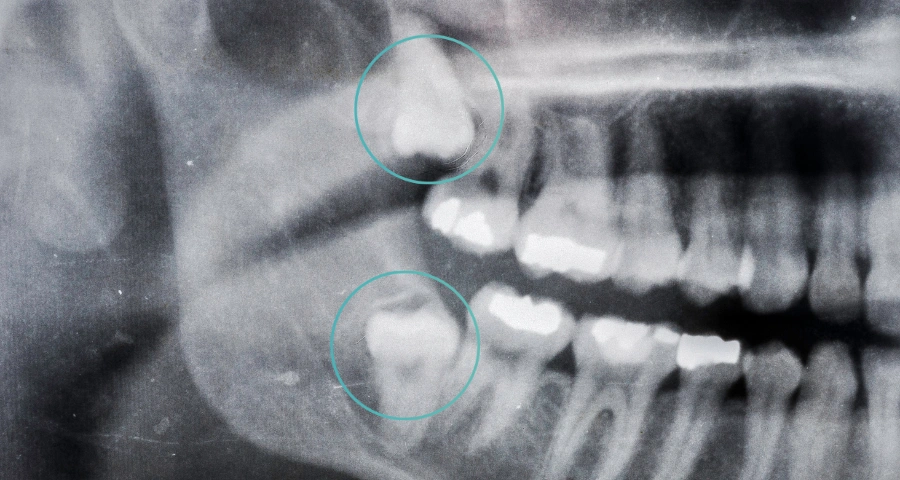

Wisdom teeth are the third set of molars that usually begin to appear between the ages of 18 and 25, though some people may never develop them at all. Around one in four Australians will develop at least one impacted wisdom tooth during young adulthood, often because there simply isn’t enough room in the jaw for these final teeth to emerge comfortably.

If your wisdom teeth are growing straight and have space to emerge, they may not be causing issues. But it’s impossible to know without an x-Ray showing the position and direction of each tooth. For peace of mind, a professional assessment with your dentist can confirm this.

At Revive Dental, we combine thoughtful assessment with personalised care. Our experienced clinicians will examine your mouth and take diagnostic imaging to see their position and how they’re developing. We explain the options clearly and talk through your proposed plan — including sedation and funding options if required — so you feel informed and supported every step of the way.